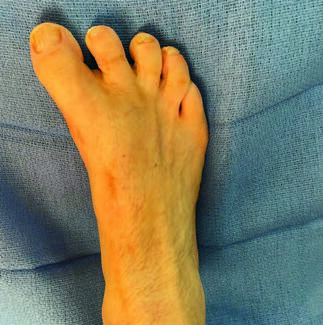

Jeffrey E. McAlister, DPM, FACFAS; Keegan A. Duelfer, DPM

Interest continues to grow in minimally invasive surgical (MIS) techniques throughout foot and ankle surgery in hopes of decreasing surgical trauma, mitigating certain risks, and perhaps allowing for earlier return to activity. Here the...